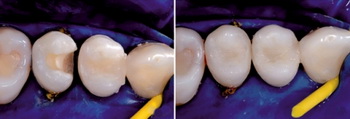

Если вкратце обрисовать основные этапы реставрации зубов композитами, среди них следует выделить: диагностику, то есть определение анатомических особенностей, структуры и цвета зубов пациента; подбор материалов, обеспечивающих желаемый результат реставрации; подготовку поверхности зуба и собственно реставрацию. В настоящее время наиболее распространенной считается многослойная техника реставрации зубов, для выполнения которой используются разнообразные виды композитных материалов. В сравнении с протезированием коронками, композитная реставрация зубов на форумах стоматологов обычно получает больше положительных отзывов: данная техника не только позволяет сократить сроки и стоимость лечения, но и является щадящей по отношению к тканям зуба. Особенно актуален такой метод при реставрации переднего зуба – за одно посещение стоматолога можно полностью преобразить внешний вид и эстетику зубов.

ЭТАПЫ РЕСТАВРАЦИИ ЗУБОВ ФОТОКОМПОЗИТОМ